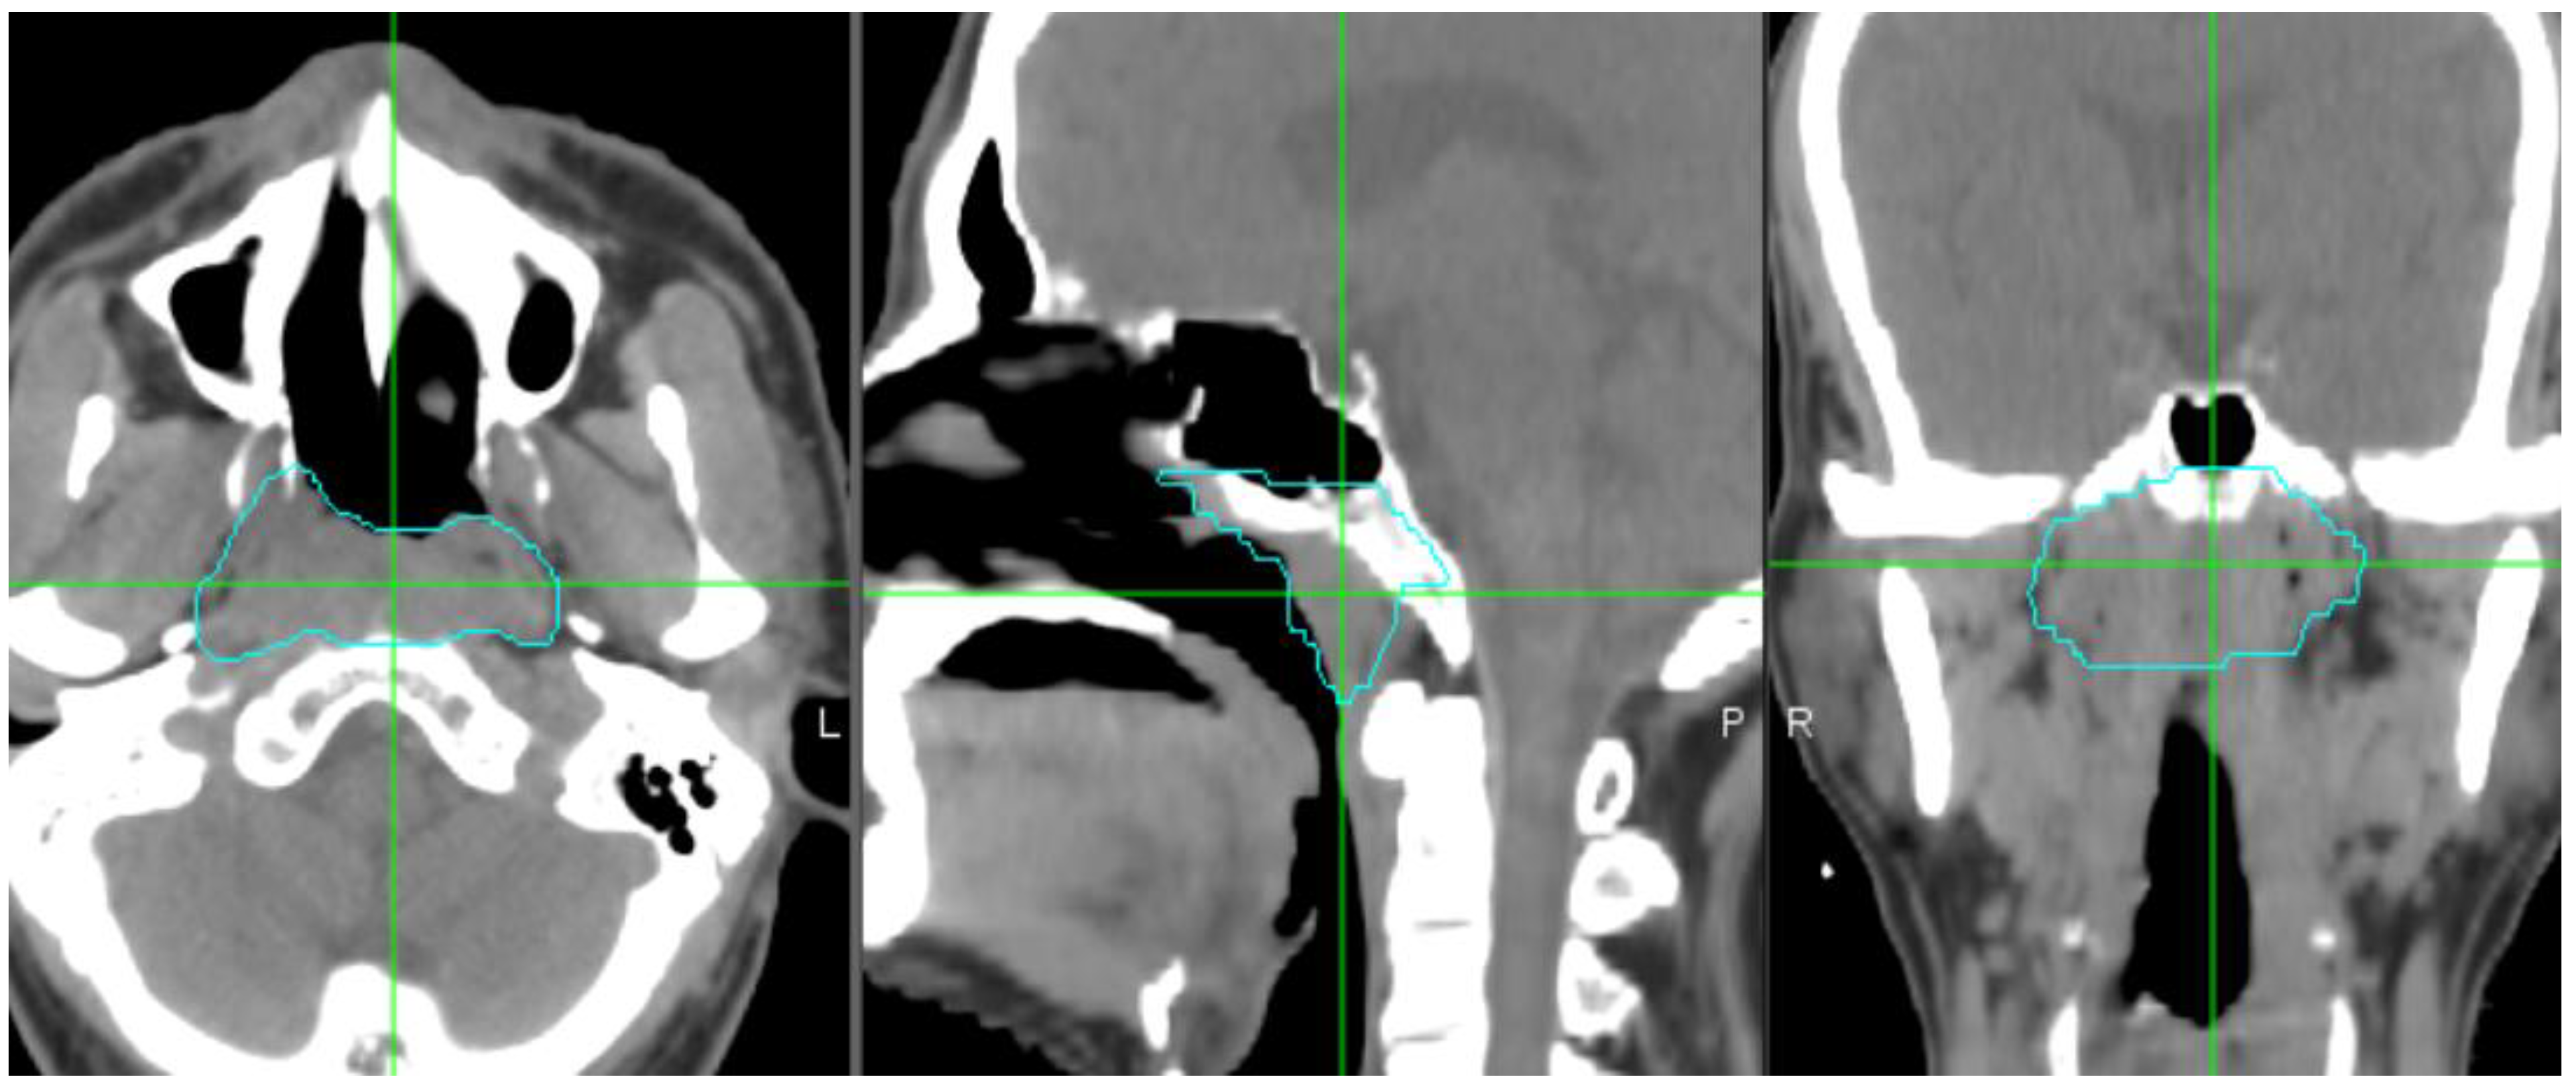

2.2. Target Delineation and Segmentation